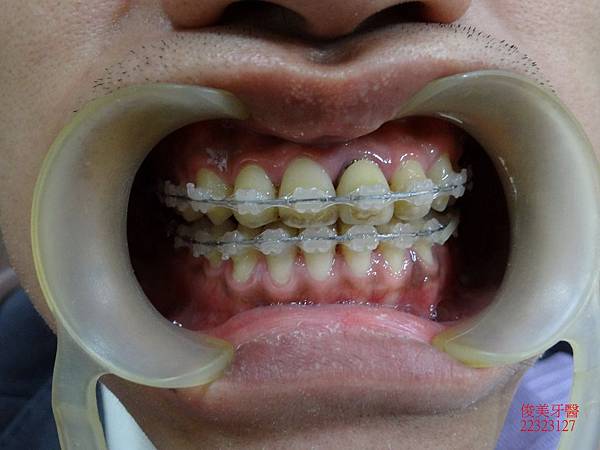

治療中~~~~

患者覺得非常開心,因為朋友在其他診所治療,都不敢相信他的療程進展如此神速~~~~~

上排牙齒已經恢復到正常咬合的位置點囉!!